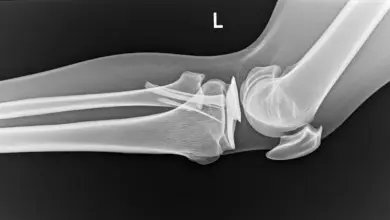

A partir daí se forma a calcificação típica da síndrome de Pellegrini-Stieda, visível na radiografia como uma imagem alongada ou nodular na parte medial do fêmur.

Nas radiografias feitas com o paciente em pé, costuma aparecer a calcificação típica, perto da origem femoral do ligamento colateral medial.